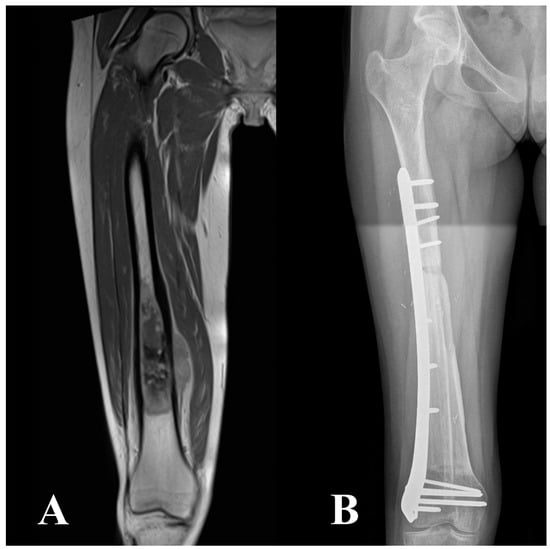

2.2. Surgical Technique, Aftercare, and Cancer Treatment

| Intercalary | 77 (10) | 58 (15) |

| Intraepiphyseal | 23 (3) | 42 (11) |

| Single bridging plate | 77 (10) | 35 (9) |